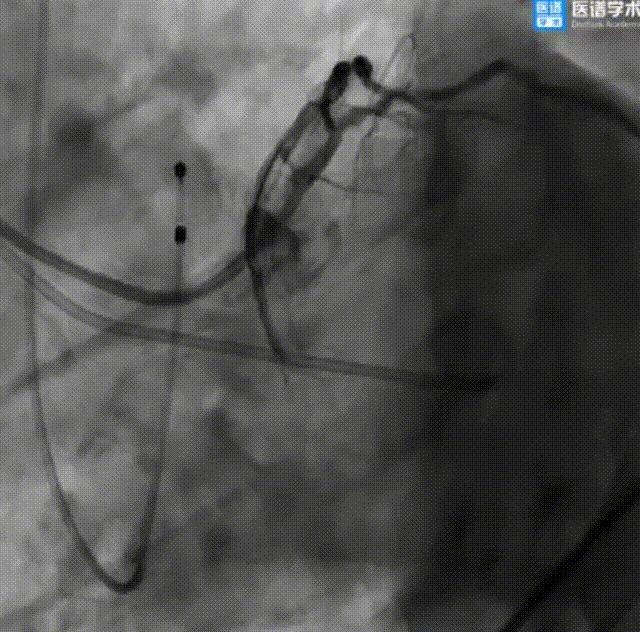

经股静脉二尖瓣球囊扩张成形术:

二尖瓣球囊扩张

PCI术后继续行经股静脉二尖瓣球囊扩张成形术,经右股静脉送入鞘管及导丝穿刺房间隔后,通过导引鞘导入二尖瓣球囊扩张系统,经食道超声确定后,使用21 mm二尖瓣球囊于二尖瓣处进行扩张,术后即刻超声提示跨二尖瓣平均压差4 mmHg,二尖瓣轻度反流。